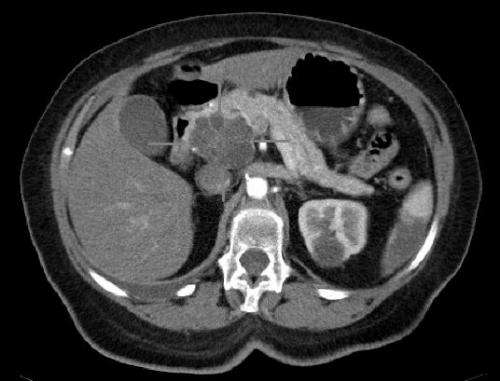

在本研究中,手术中取患者肿瘤样本,并移植到小鼠中以生长成新的胰腺肿瘤。